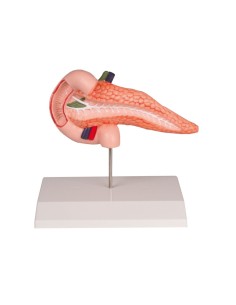

3B Modèle scientifique et anatomique : Pathologies de l'intestin K55